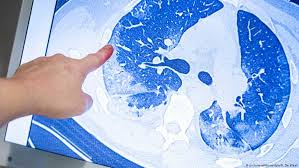

أطباء ألمان يرصدون غيوما غريبة في الرئة لدى مرضى كورونا صحة معلومات لا بد منها لصحة أفضل Dw 25 04 2020